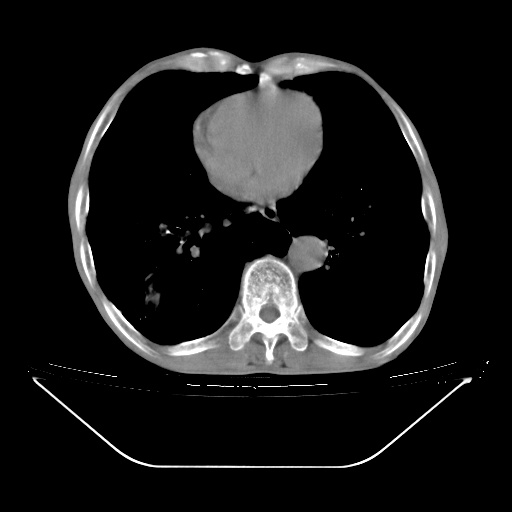

以下是引用zsl6918在2008-8-25 21:55:00的发言:[br]符合右肺周围性肺癌并肺内转移,左肺结核球。双肺肺气肿。腰椎附件转移。

以下是引用随光逐影在2008-8-25 22:03:00的发言:[br]1)考虑右肺下叶周围性肺癌并肺内转移,腰椎附件转移。2)左上肺结核(结核球形成)。3)双肺肺气肿(多发肺大泡形成)。4)双肺门区及纵隔内多发淋巴结钙化。